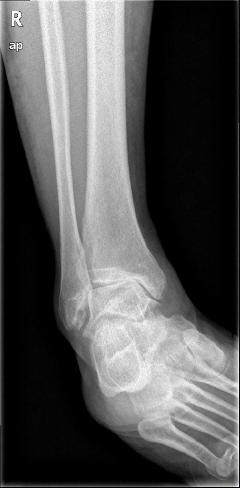

Ποδοκνημική - Ασθενής 2 - Προεγχειρητικά